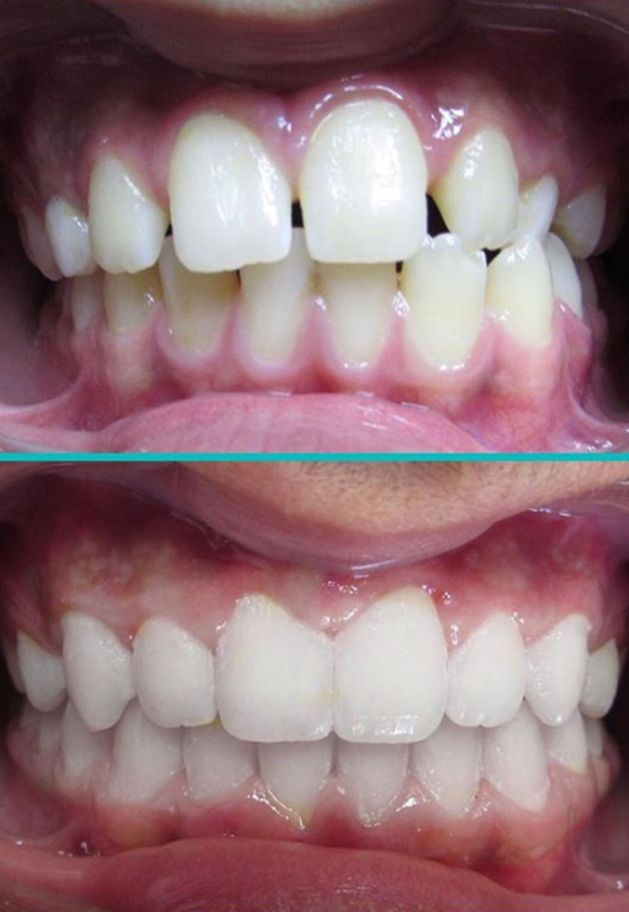

ΛΗΨΗ ΚΑΙ ΑΞΙΟΛΟΓΗΣΗ ΦΩΤΟΓΡΑΦΙΩΝ

Με την λήψη των φωτογραφιών (ενδοστοματικών και εξωστοματικών), ο Ειδικός Ορθοδοντικός έχει την δυνατότητα να αξιολογήσει το πρόσωπο του ασθενούς και να εκτιμήσει πως ενδέχεται να επηρεάσουν οι αλλαγές στο χαμόγελο την γενικότερη αισθητική του προσώπου ώστε να επιτευχθεί το καλύτερο δυνατό αποτέλεσμα. Επιπλέον δύνεται η δυνατότητα περαιτέρω αξιολόγησης της ορθοδοντικής ανωμαλίας ενδοστοματικά.